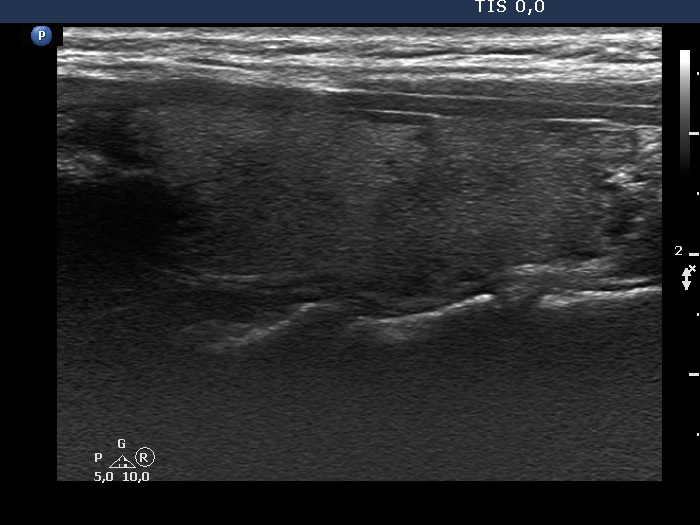

Two years after the first visit (second row of images):

Clinical presentation: The patient requested evaluation of neck complaints. Her left thyroid became painful and she became feverish 3 weeks ago. She suffered from upper airways infection 2.5 months before the onset of complaints.

Palpation: Both lobes became hard. The right lobe was very sensitive while the left was painful on palpation.

Laboratory tests: TSH 0.02 mIU/L, FT4 30.7 pM/L, CRP 51.8 mg/L.

Ultrasonography: The thyroid became minimally hypoechoic and more hypoechoic areas have appeared in both lobes. The echogenicity index was 20% and 50%, right and left lobe, respectively. The vascularity was decreased.

Suggestion. Steroid therapy.